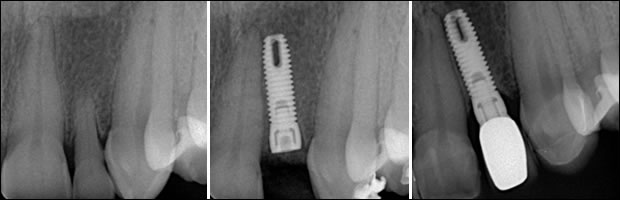

Fig7: Site #10, the retained decidous tooth, extraction and immediate implant placement, the final restoration respectively.